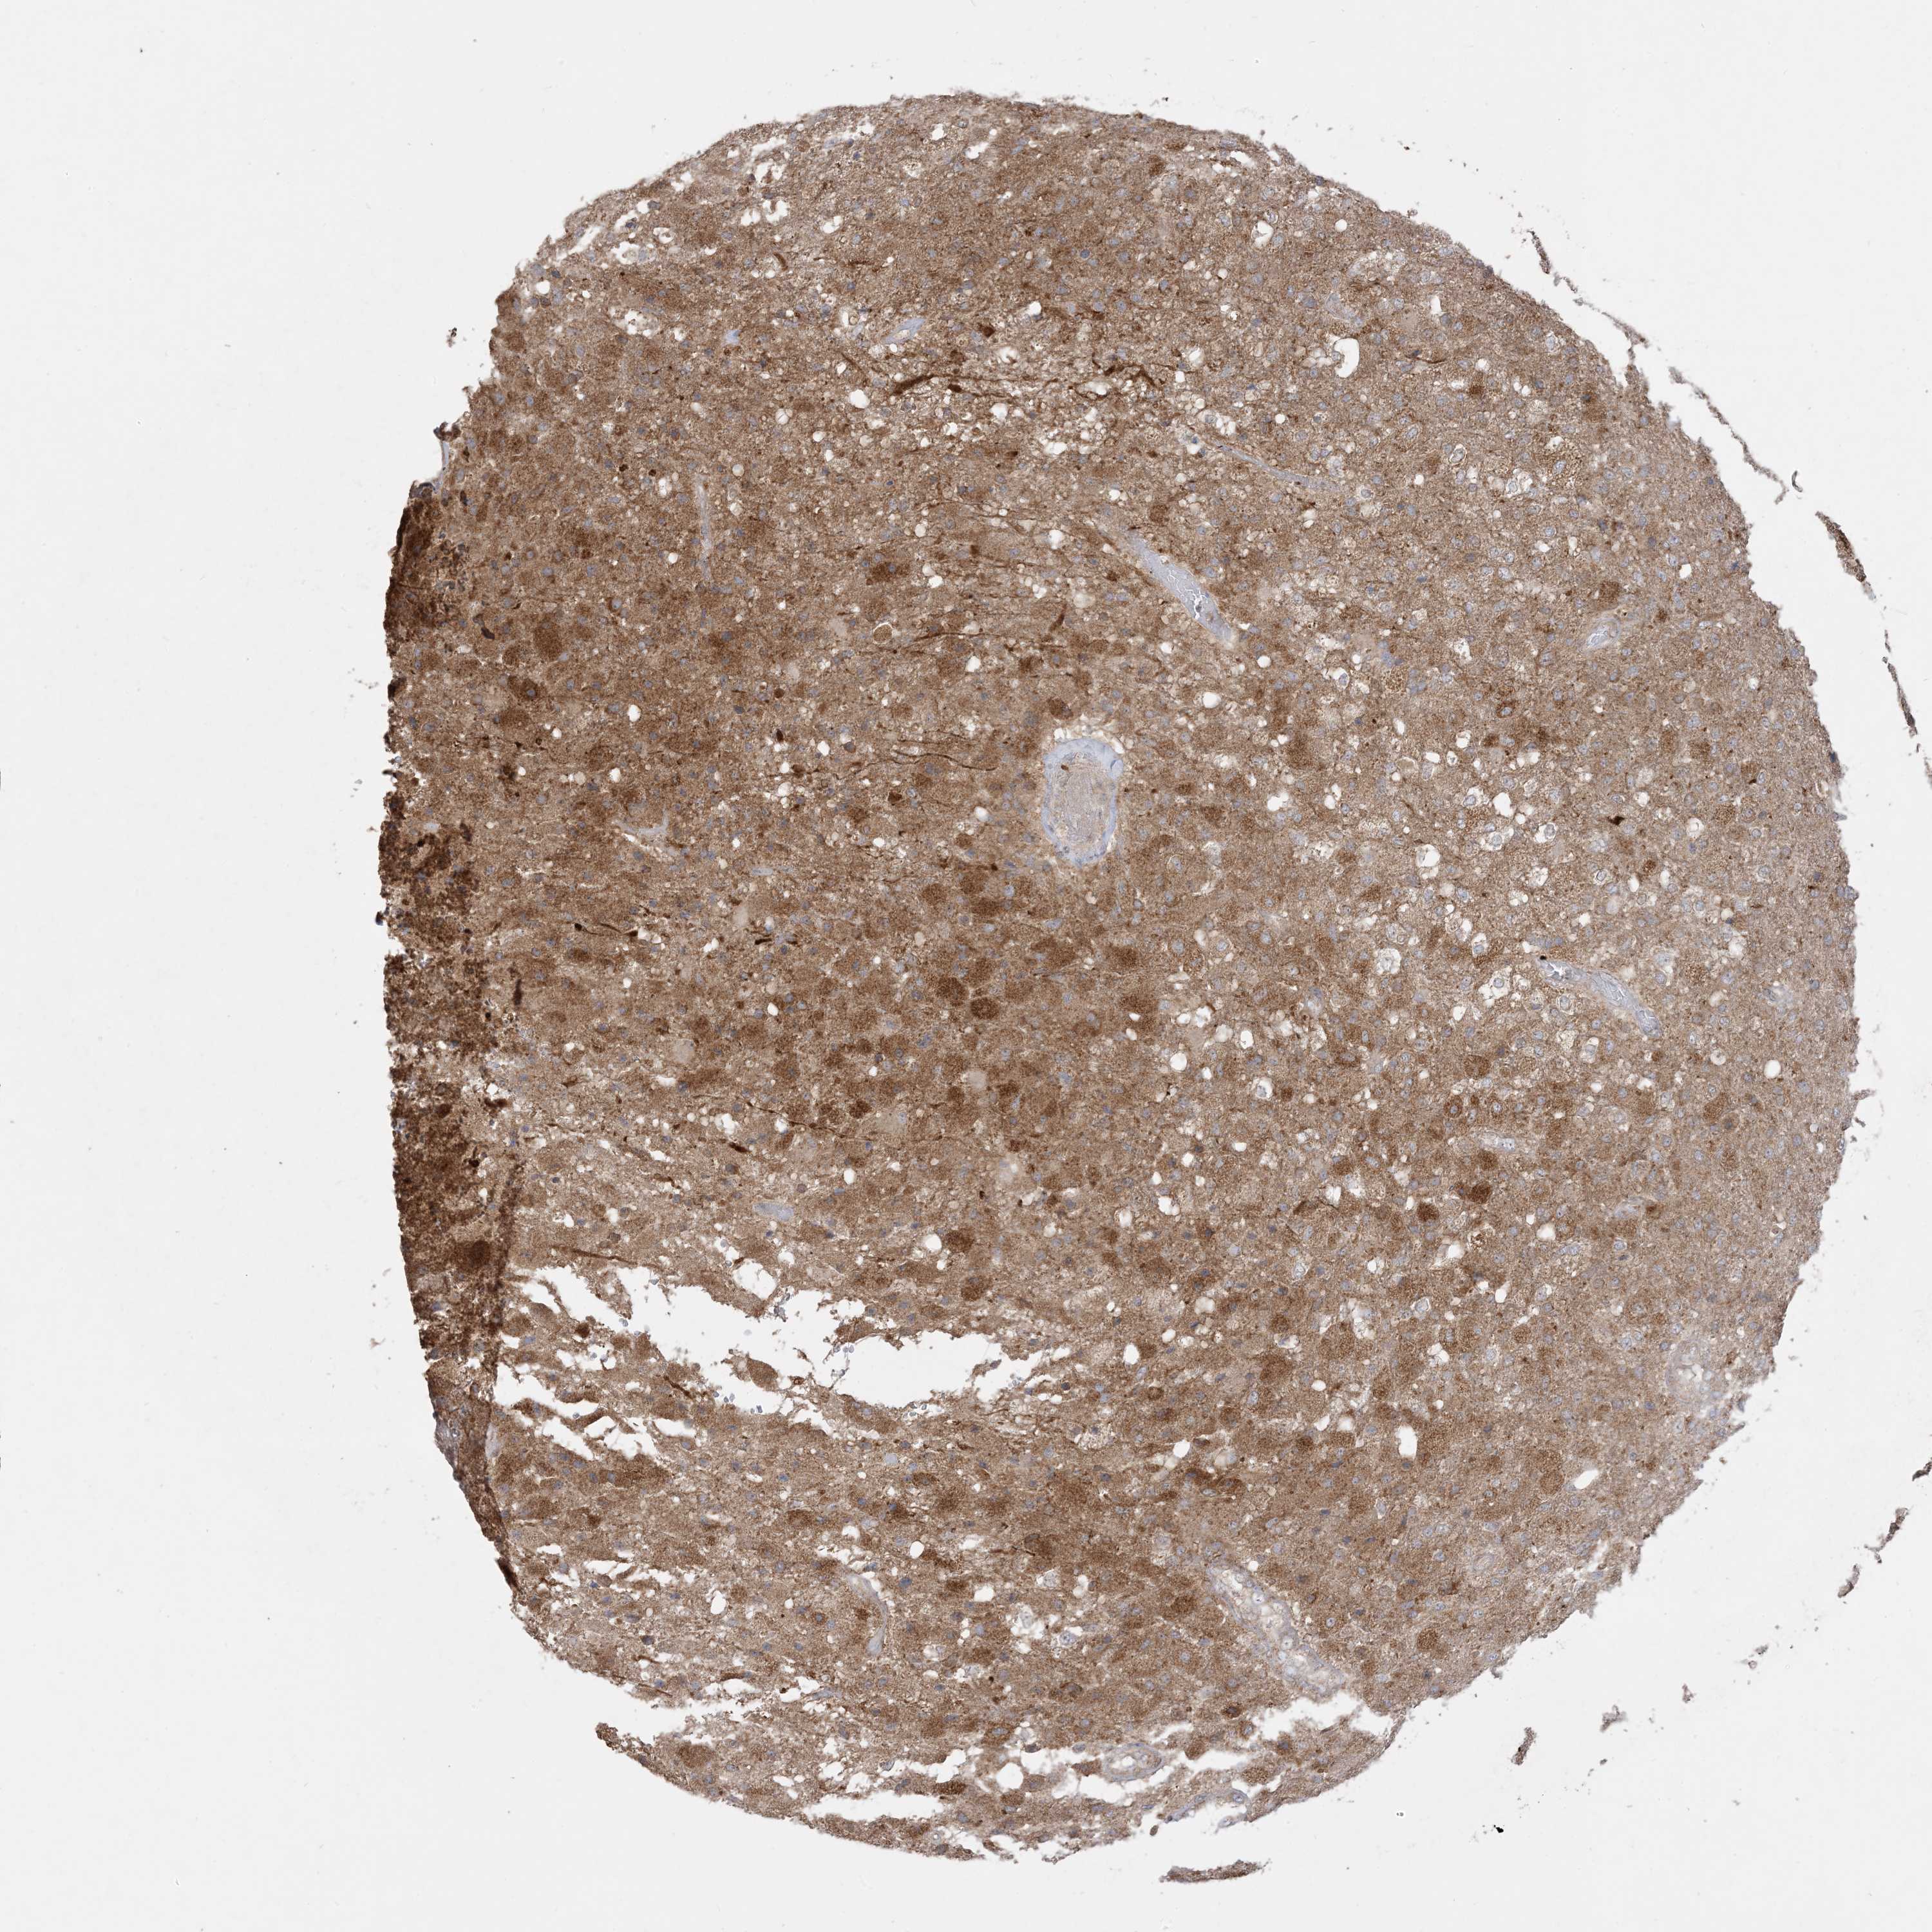

GLIOMA - Protein expressioni

A mouse-over function shows sample information and annotation data. Click on an image to view it in a full screen mode. Samples can be filtered based on level of antibody staining by selecting one or several of the following categories: high, medium, low and not detected. The assay and annotation is described here.

Note that samples used for immunohistochemistry by the Human Protein Atlas do not correspond to samples in the TCGA dataset.

Antibody stainingi

Antibody staining in the annotated cell types in the current human tissue is reported as not detected, low, medium, or high, based on conventional immunohistochemistry profiling in selected tissues. This score is based on the combination of the staining intensity and fraction of stained cells.

Each image is clickable and will lead to virtual microscopy that enables deeper exploration of all samples and also displays staining intensity scores, fraction scores and subcellular localization as well as patient and tissue information for each sample.

Antibody CAB037142

Staining

High

Medium

Low

Not detected

Intensity

Strong

Moderate

Weak

Negative

Quantity

>75%

75%-25%

<25%

None

Location

Nuclear

Cytoplasmic/membranous

Cytoplasmic/membranous,nuclear

Glioma, malignant, High grade

Glioma, malignant, Low grade